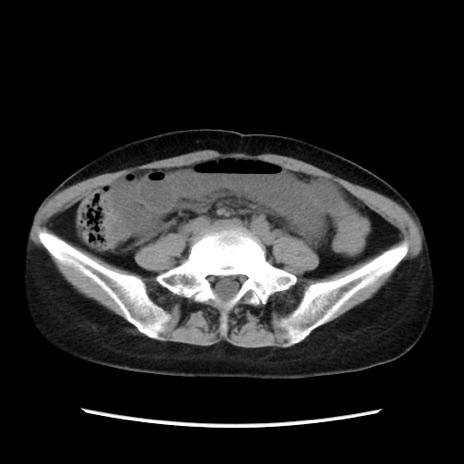

症例32(横断像)

【症例】40歳代 女性

【主訴】上腹部痛、嘔気・嘔吐

【現病歴】約9時間前頃から急に上腹部痛、嘔気、嘔吐が出現。改善しないため救急要請。

【既往歴】子宮頚癌(広汎子宮全摘術、放射線療法)、腸閉塞

【身体所見】腹部:平坦、軟、腸雑音亢進、上腹部を中心に腹部全体に圧痛あり。

【データ】WBC 8400、CRP 0.03